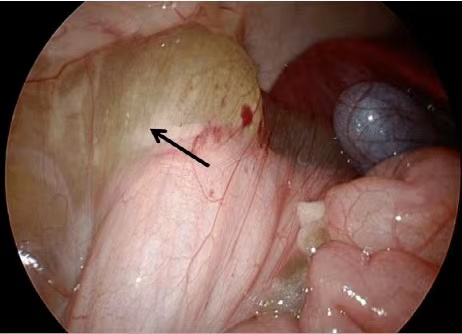

考虑患者年轻,如果行常规手术会造成较大创口,决定实施全腹腔镜肿物切除术。术前对手术风险、麻醉管理、补液及抗生素使用、围术期管理等问题进行深入研讨,并围绕可能出现的术后并发症一一做好预案。术中在胃镜的定位下,实现了腹腔镜肿瘤的精准扩大切除,手术过程非常顺利,用时2个多小时,出血仅50ml。